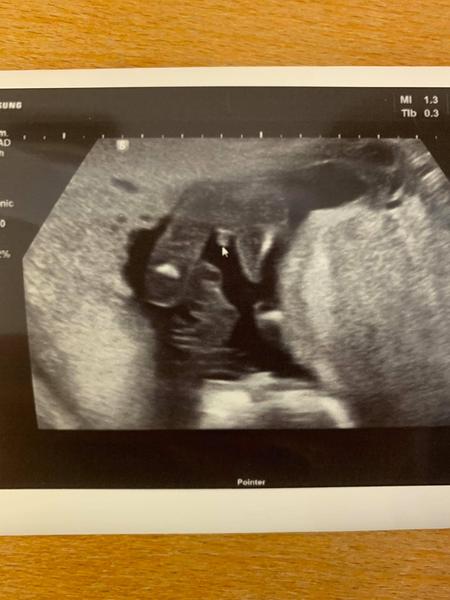

Holka nebo kluk podle ultrazvuku v17.tt?

Ahojda... co myslite holka nebo kluk ??? chci udelat priteli radost, ale nejsem si jista odpovedi doktora 🙂

Ja vim...ale proste mi to prislo u nej tak rychly, ze ted nechci zklamat, ze reknu tohle a nakonec to byla pupecni snura treba :D :D tak se prece nebudete zlobit, ze jsem to zkusila nooo se zeptat tu :D :D

kluk 🙂

dekuji moooccc ja furt nervy jestli to neni pup snura nebo tak :D :D :D me tohle alespon uklidni a muzu udelat prekvapko synovi a priteli po komentarich 🙂

@barulilinka nemate zac. To ze to bude kluk mam potvrzene od 2 doktoru + uz u 1. Screeningu rekli na 60% kluk. Jelikoz se fotky temer nelisi, tak gratuluji 😁 mate taky kluka